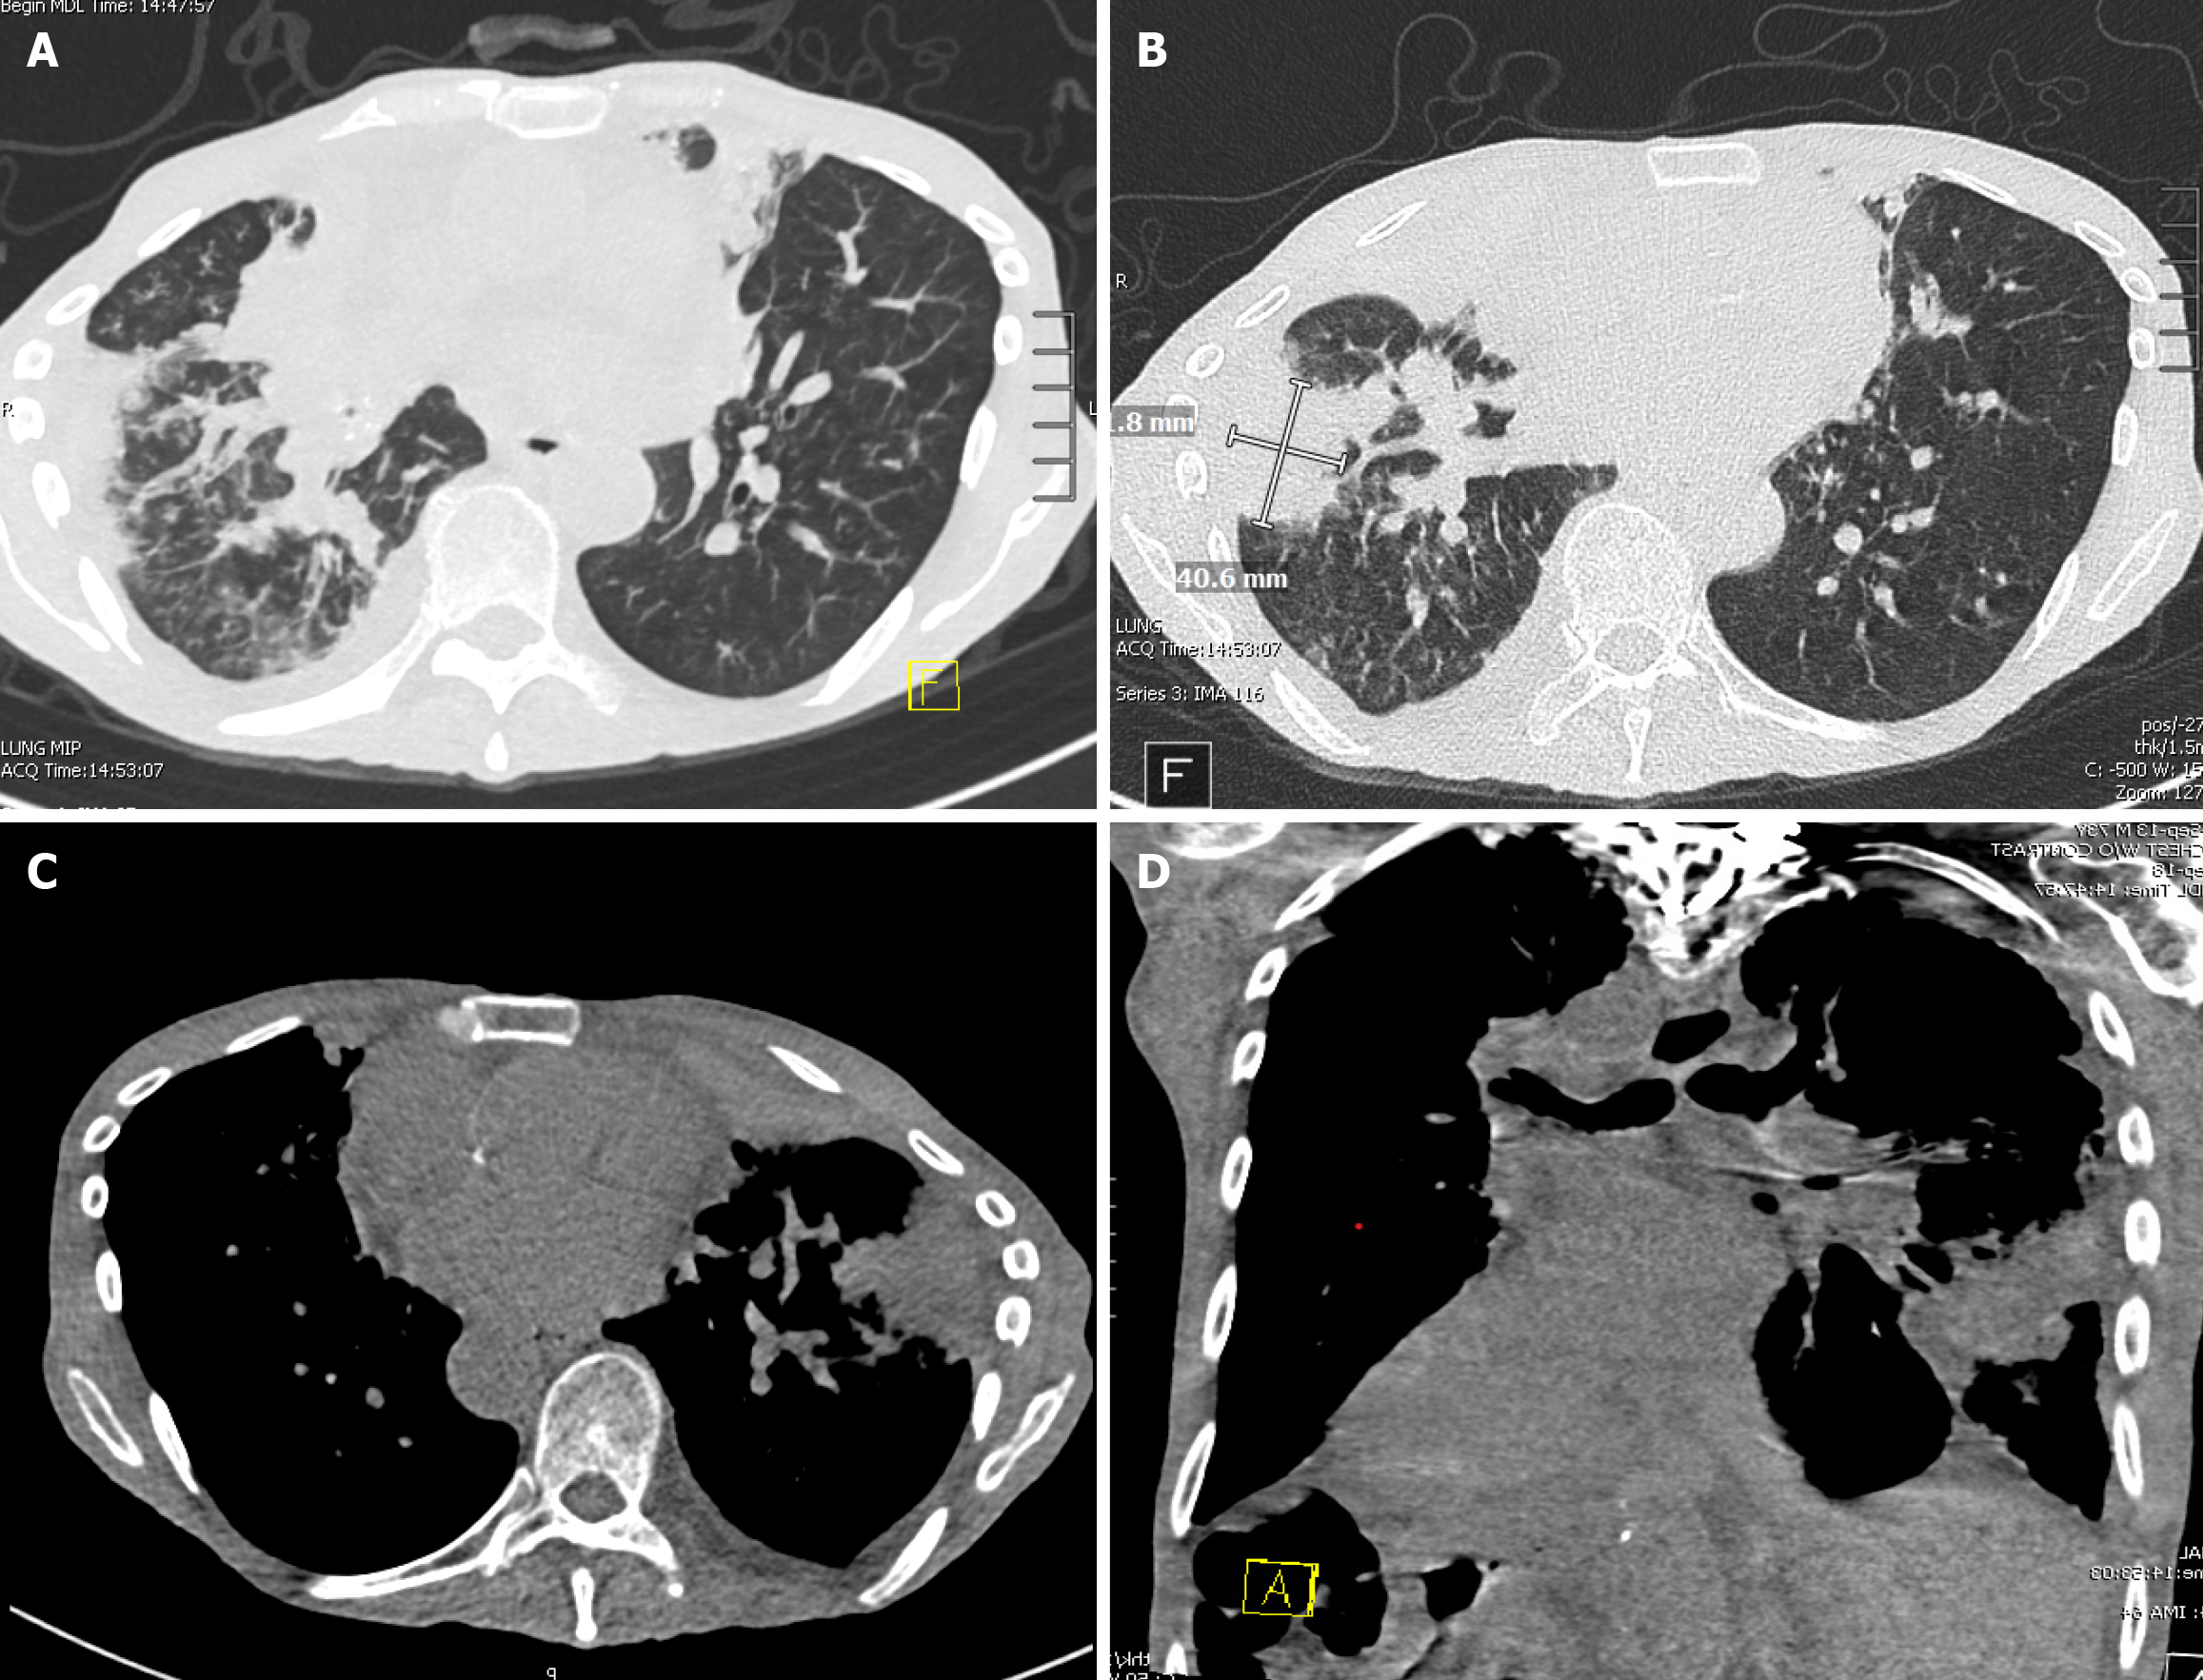

Figure 2 Computed tomography of the abdomen and pelvis without contrast showing new and worsening consolidative opacities in both lungs, which include a consolidative opacity in the right hilum that appears to be enlarging and a new mass-like consolidative opacity in the right lower lobe.

A: Axial lung window showing consolidative opacities, more notable on the right; B: Axial lung window showing a right lower lobe lung mass; C: Axial view showing consolidative opacities in the left lung; D: Coronary view showing consolidative opacities, predominantly in the left lung. Additionally, there is a new right-sided pleural effusion and extensive airway thickening with numerous occluded bronchi.